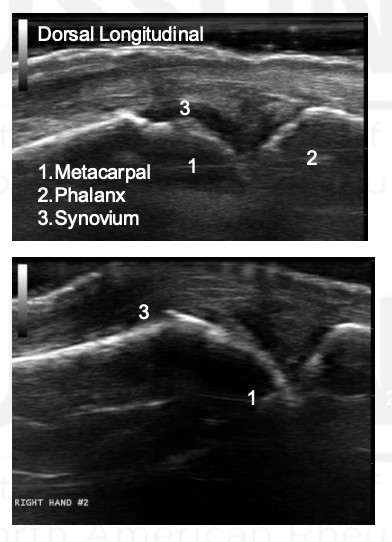

What is the arrow pointing to?

Synovial Distension

What grade is the synovial hypertrophy?

Grade 0

Grade this synovial hypertrophy

Grade 1: minimal within imaginary line between joint edges

Grade 2: moderate, extends over joint line with concave appearance

Grade 3: severe, extends beyond joint line with convex appearance